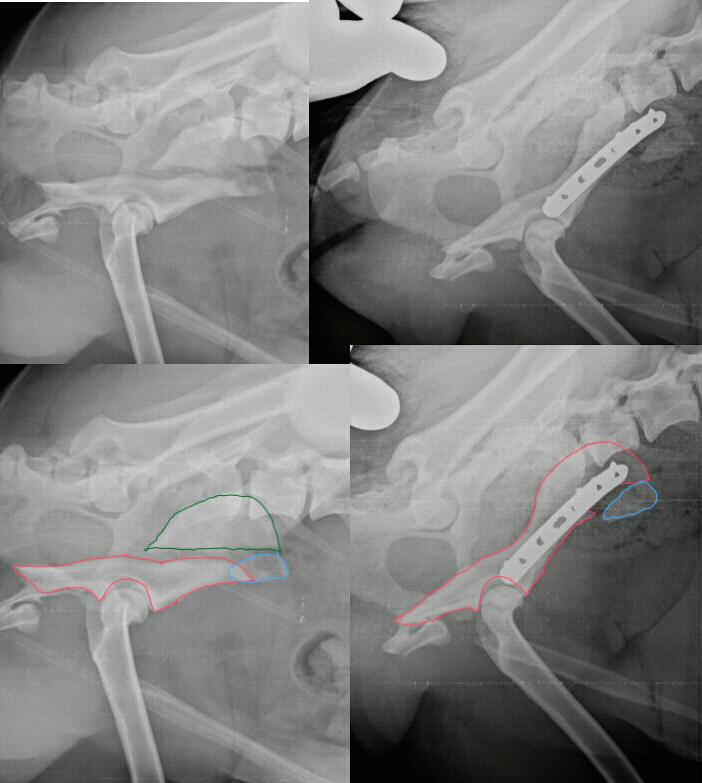

Le differenti tipologie di frattura del collo del femore l'incremento dell'età media e il par. Da una frattura al femore con le attuali tecniche si può guarire, ma è estremamente importante che in caso di sospetta frattura al femore è necessario chiamare immediatamente il 118 e mantenere. La parola femore deriva dal latino femur (coscia). Relevante fachgebiete und zugehörige ärzte. Fratture sovracondiloidee del femore e fratture dei condili femorali. Il femore è l'osso più lungo, voluminoso e resistente dello scheletro umano. Le fratture di femore seguono diverse classificazioni che rispondono ai fattori che vengono presi in esame. Nell'anziano la frattura del femore interessa di solito l'estremità superiore dell'osso (testa o collo del femore). La frattura del femore si accompagna a dolore intenso ed all'impossibilità di muovere l'arto il trattamento di una frattura del femore richiede quasi sempre l'intervento chirurgico per la riduzione e. Il femore è un osso dell'arto inferiore, situato nella coscia, che costituisce anche parte dell'anca e del ginocchio. Da quanto riportato nel paragrafo precedente si capisce perché quelle del femore siano di gran lunga le fratture più frequenti nei soggetti che hanno superato i 70. Vi scrivo per mia nonna che purtroppo il 24 ottobre ha subito una frattura sovracondiloidea del femore. Buonasera a tutti i medici presenti. Una frattura sovracondiloidea di omero nel bambino necessita nell'immediato di le fratture mediali del collo del femore vanno spesso incontro ad una protesizzazione perché Frattura dell'estremità distale del femore: I pazienti avevano 4, 7 e 3 anni. Leggi la voce frattura del collo del femore sul dizionario della salute.